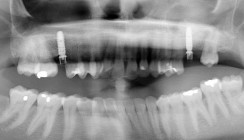

Radiologisch war ein signifikanter Knochenabbau um das Implantat zu verzeichnen (Abb. 2). Die klinische Untersuchung zeigte klassische Anzeichen einer periimplantären Entzündung: Bluten auf Sondieren (BOP+), erhöhte Sondierungstiefen (ST) und eine lokale Schwellung der Mukosa (Abb. 3–5). Das primäre Ziel war es, den Entzündungsprozess nicht chirurgisch zu stoppen und ein biologisches Milieu zu schaffen, das eine langfristige Stabilität ermöglicht. Der Implantataufbau wurde derzeit am Halsbereich zu dick ausgearbeitet und wies aus diesem Grund kein optimales Emergenzprofil auf. Nach der Eingliederung der definitiven prothetischen Versorgung kann es – insbesondere bei dicken suprakrestalen Weichgeweben – vorkommen, dass sich das Weichgewebe an die Kronenkontur adaptiert, was biologisch nicht immer gut toleriert wird. In der Folge kann es zu einer lokalen entzündlichen Reaktion kommen. Aus diesem Grund war zudem eine Umgestaltung der Krone vorgesehen.